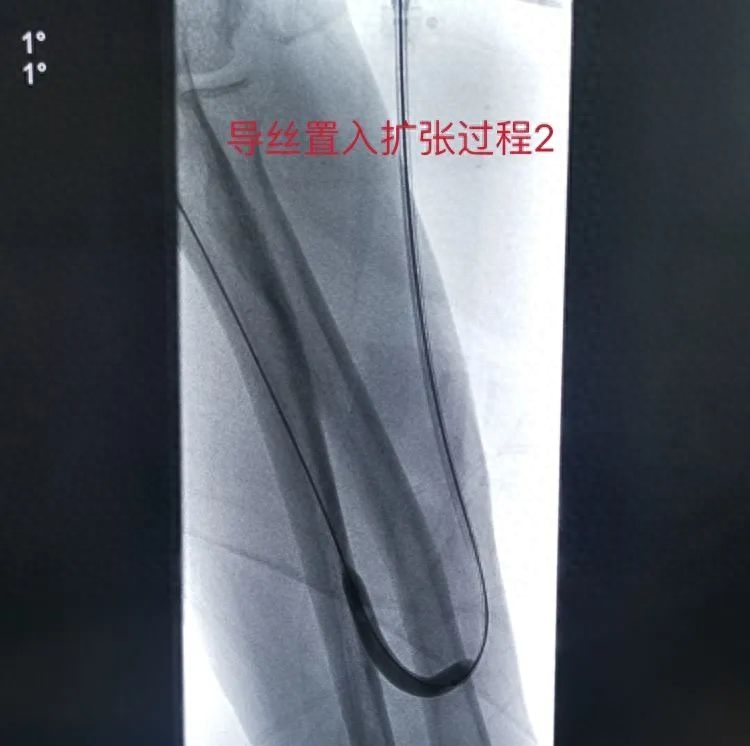

手术中,曾庆福博士和刘志华医师耐心继续置入导丝,利用穿刺鞘反复负压抽吸血栓,采用高压球囊扩张对狭窄处继续逐段扩张。

最后再次经采用高压球囊逐段扩张狭窄处,扩张后造影见吻合口及静脉段狭窄处明显好转,头静脉充盈良好,震颤清晰,手术顺利。